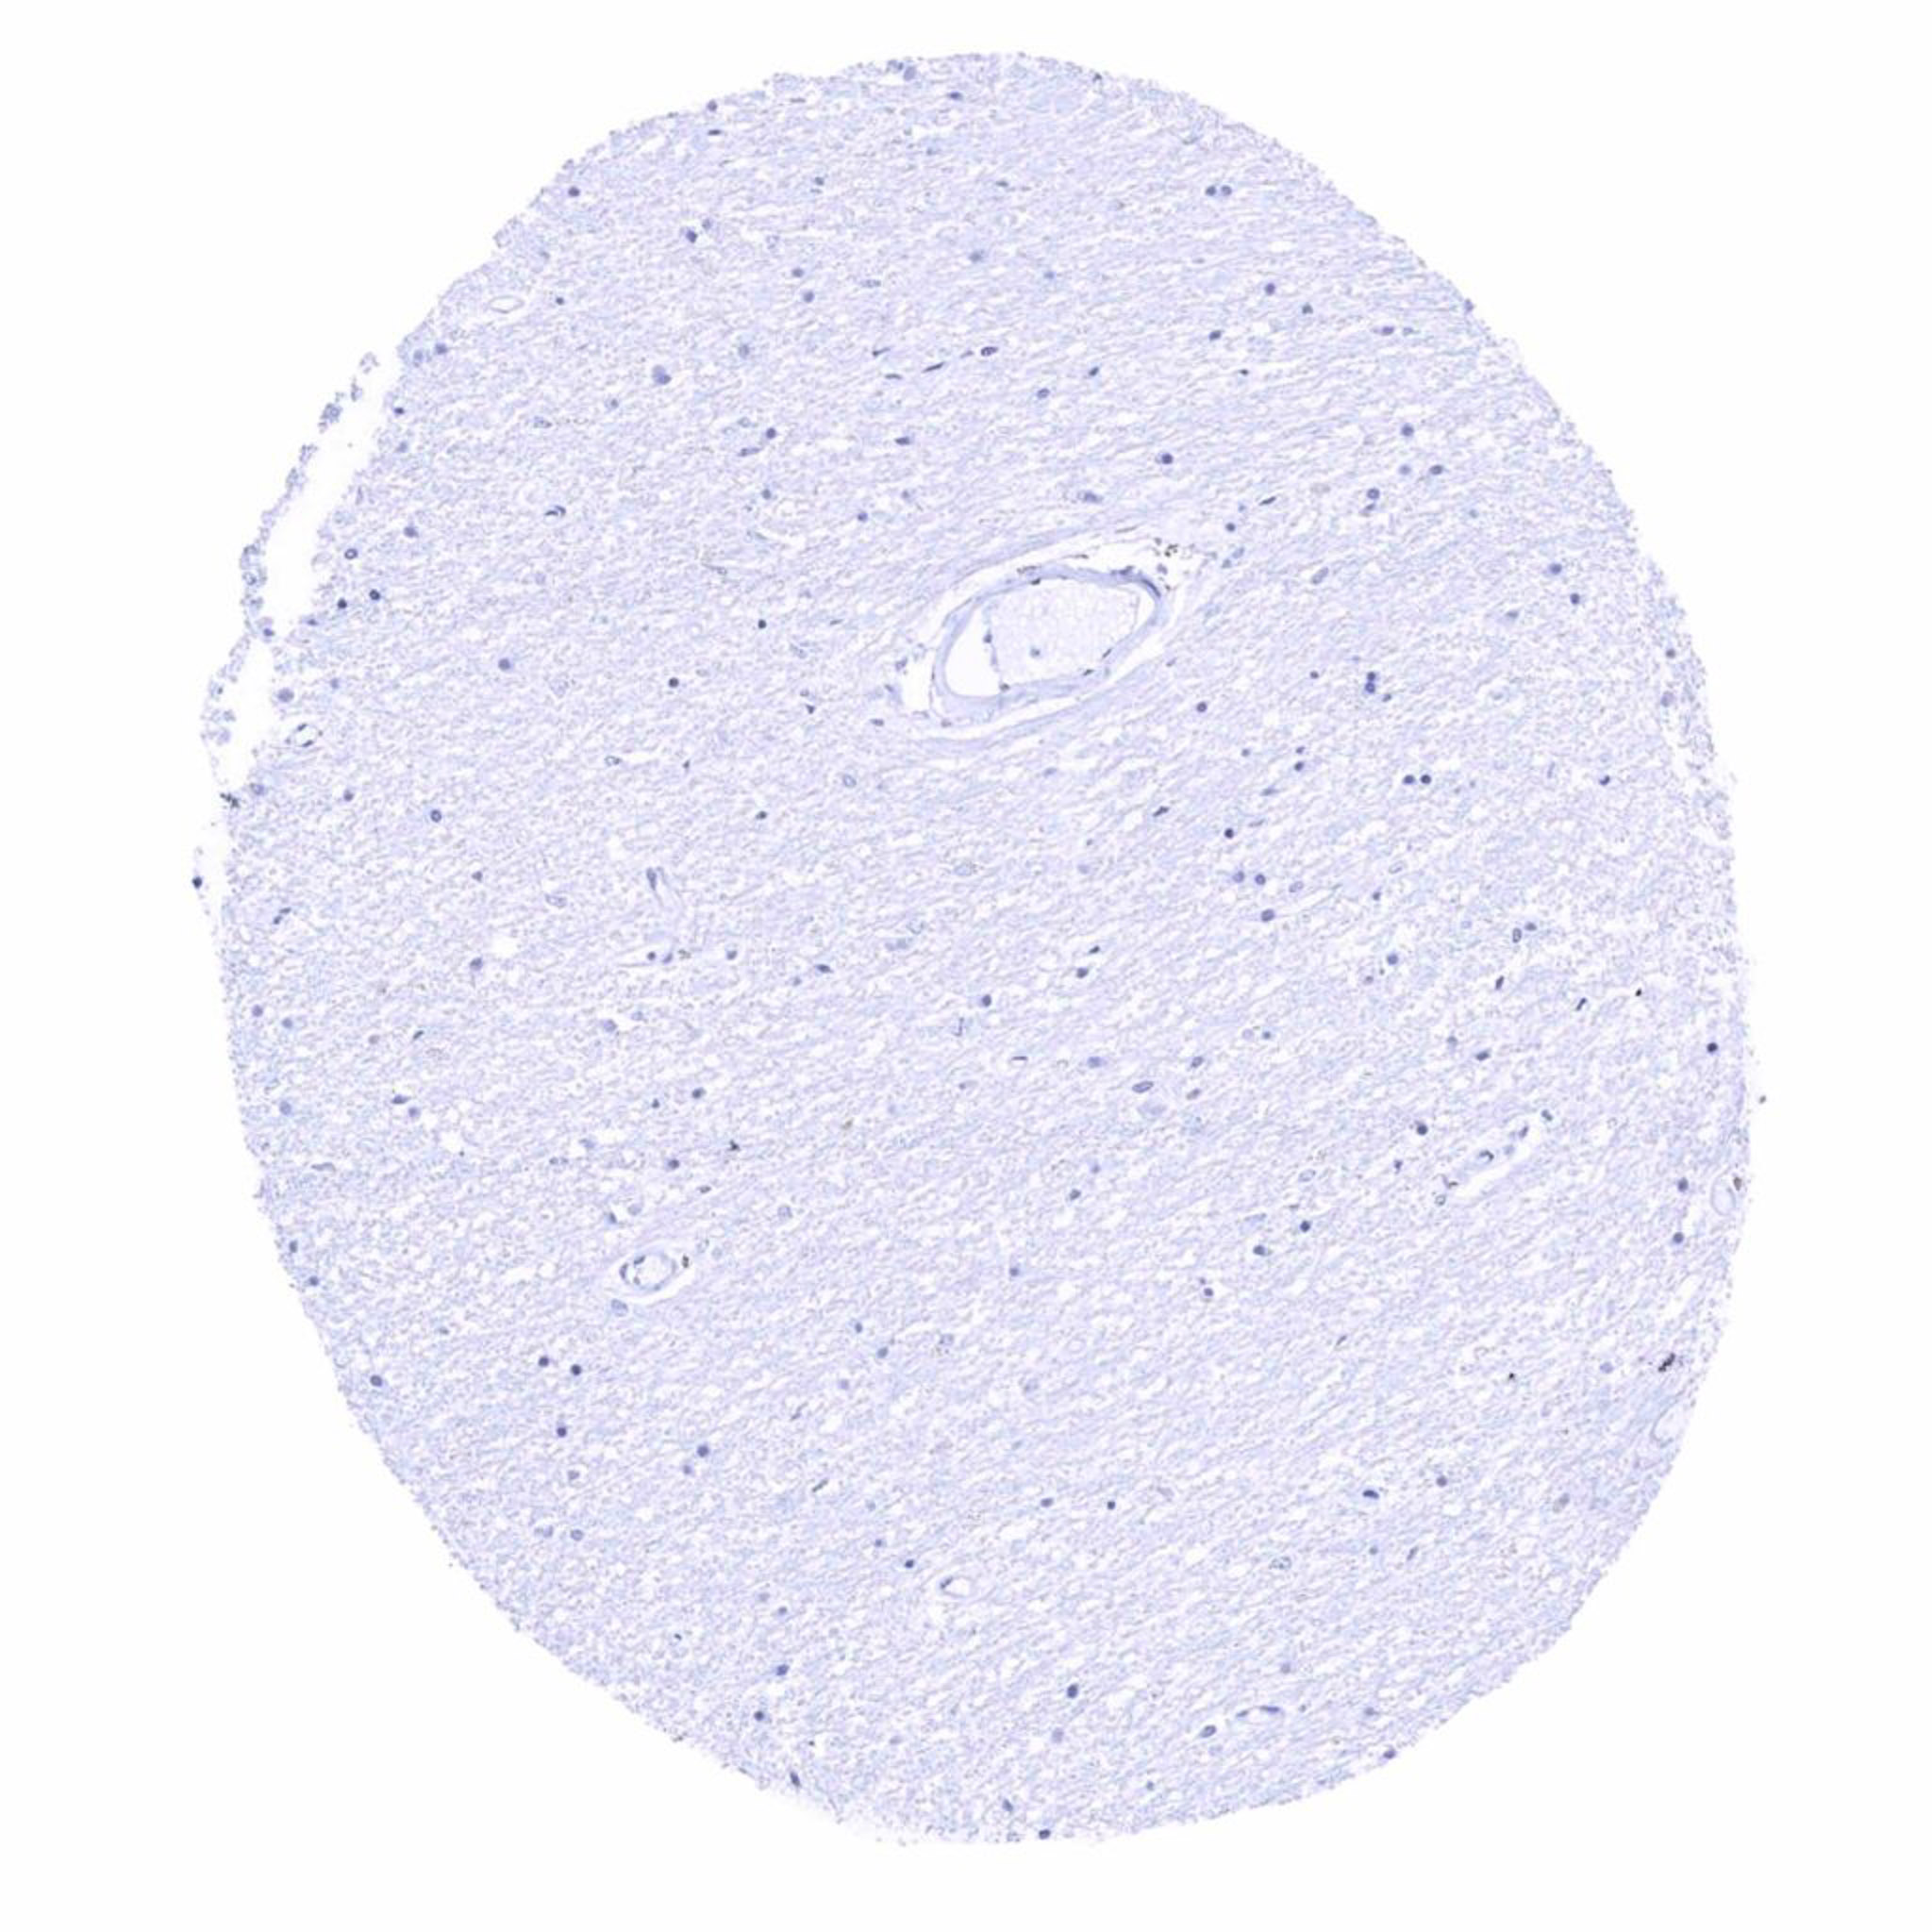

Pancreas – TRPS1 staining is lacking in this sample